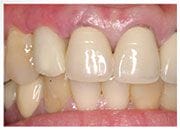

陳小姐是一位美貌與才氣兼具的事業女強人,在一次晚宴中,已經做了十多年的門牙假牙脫落,陳小姐緊急求助黃醫師,立刻進行"立即式植牙" ,將已經蛀壞的牙根拔除,植入人工牙根,再做上美觀的假牙,讓陳小姐無後顧之憂的面對明日的工作。

治療後